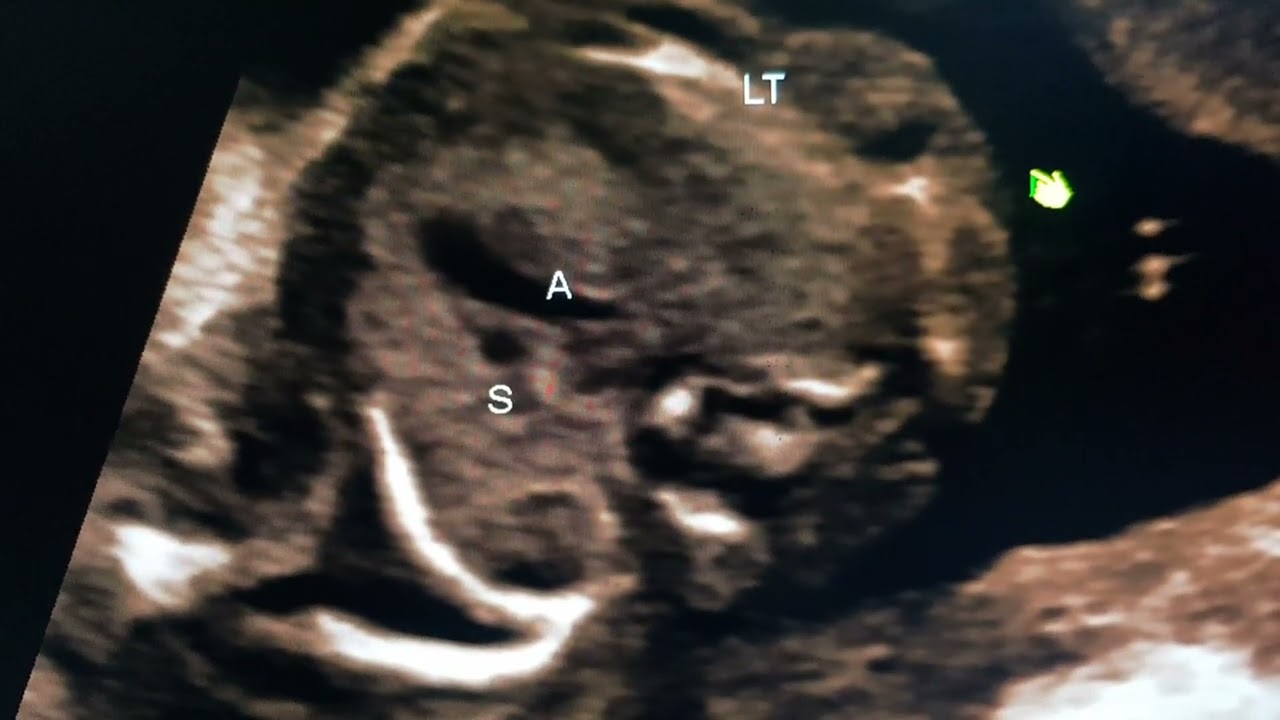

Скачать или смотреть Урок по фетальной нейросонографии, проводимый доктором Прадипом в рамках серии «Refer».

Урок по фетальной нейросонографии, проводимый доктором Прадипом в рамках серии «Refer».

Обучение проведению фетальной нейросонографии в случае двусторонних кист сосудистого сплетения.